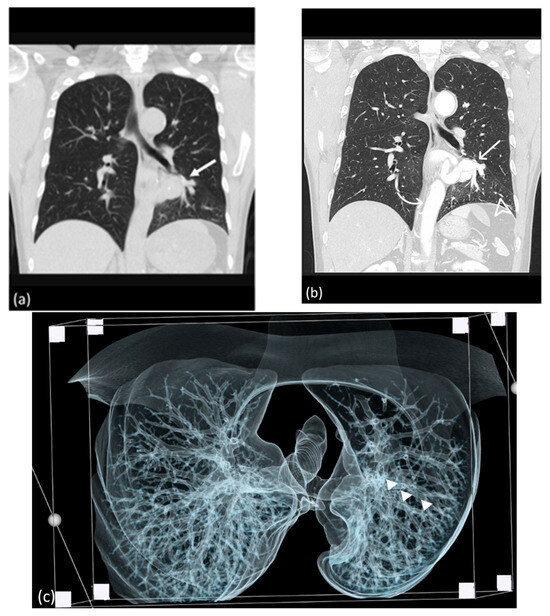

A 29-year-old man with no known pulmonary disease presented to a cardiovascular clinic with complaints of hemoptysis, chest tightness, and numbness in all four limbs during exercise. Pulmonary CTA revealed an aberrant left pulmonary artery originating from the descending thoracic aorta and supplying the left lower lobe and an engorged inferior pulmonary vein leading to the left atrium (Figure 7). The patient opted for observation at the clinic.

Figure 7.

Reconstructed 3D CT image (a) and CTA image (b) displaying the engorged aberrant pulmonary artery (arrow) originating from the descending aorta.